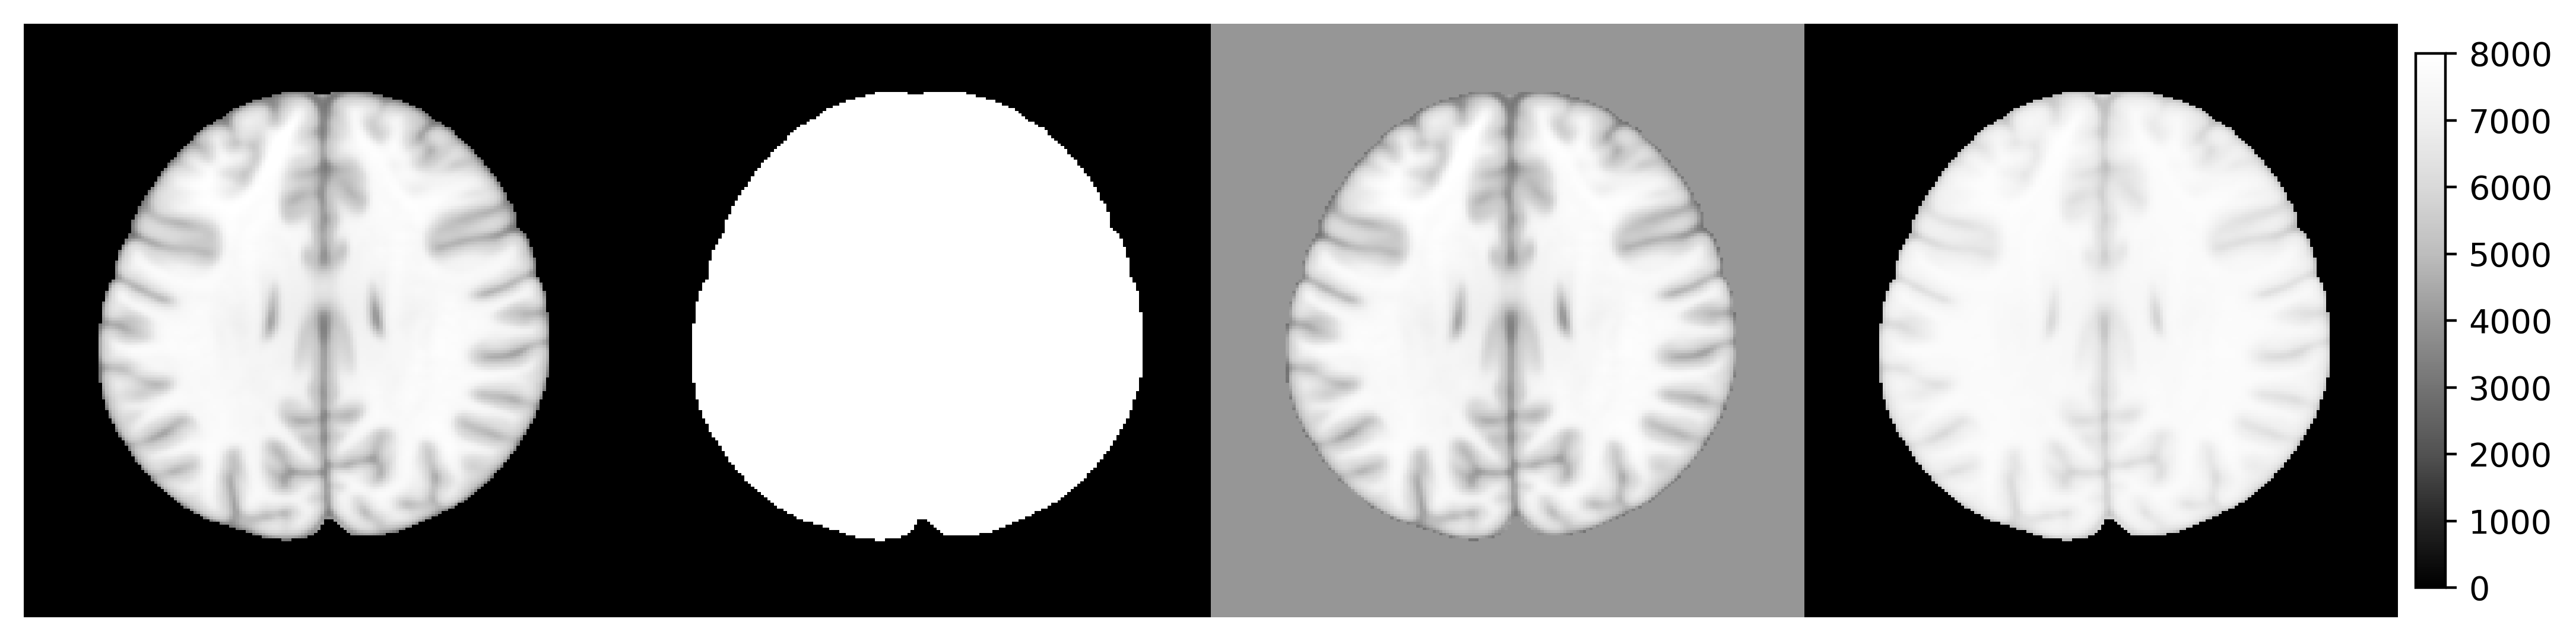

In Python, operators on ANTsImage, such as img > 5 are defined. Such operators is being supported in R as S3 generic functions. Don’t worry if you don’t know what is S3 generic, see the following examples:

library(rpyANTs)

image <- ants$image_read(ants$get_ants_data('mni'))

print(image)

dim(image)

range(image)

y1 <- (image > 10) * 8000

y2 <- image

y2[y2 < 10] <- 4000

y3 <- log(image + 1000)

y3 <- (y3 - min(y3)) / (max(y3) - min(y3)) * 8000

ants_plot_grid(

list(image, y1, y2, y3),

slices = 100, shape = c(1, 4),

vmin = 0, vmax = 8000

)